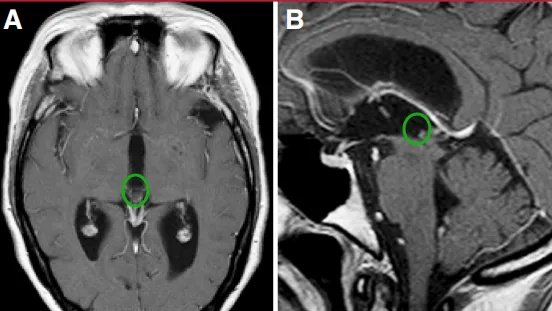

49岁女性,主诉头痛、恶心及呕吐。磁共振成像(MRI)显示一小型、明显强化的占位性病变阻塞中脑导水管,导致三脑室性脑积水(图1)。

经右侧室间孔(Monro孔)行内镜下手术(图A)。术中实现病变全切除(图B)。

术后MRI复查示病灶无残留,脑积水已完全缓解。